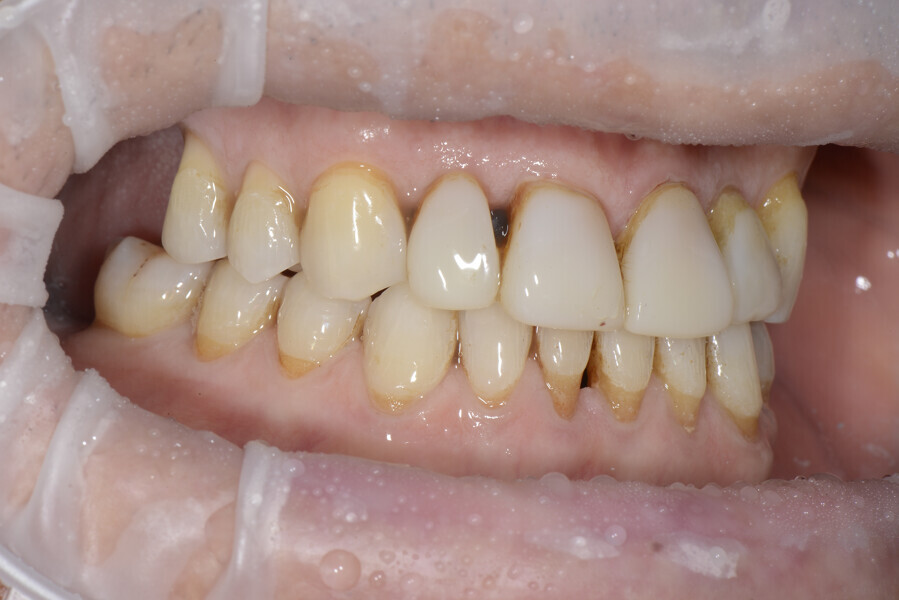

The 58-year-old patient wished to improve his oral aesthetics and function, complaining of mobility of the posterior teeth and wear of the anterior teeth. After data collection, a very complex situation was identified (Figs. 11–13):

1. severe periodontitis with poor prognosis of some teeth;

2. anterior crossbite;

3. severe wear mainly of the anterior teeth and compensatory eruption;38

4. atypical swallowing and lower posture of the tongue at rest;

5. masticatory dysfunction during the mastication test; and

6. no significant signs of temporomandibular disorder.

After the first phase of aligner treatment, we had achieved better inter-arch coherence, better maxillary arch expansion, and some space for improving the anterior tooth proportions restoratively (Fig. 19). We then temporarily restored the anterior teeth directly with composite, closing the spaces, improving the tooth proportions and further increasing the maxillary arch expansion (Fig. 20). We used restorative arch expansion to reduce the orthodontic destabilisation of the teeth to achieve the correct inter-arch coherence and retain the teeth in the cortical bone.38 A refinement aligner phase was undertaken to improve the final alignment of the gingival zenith and to improve the inter-arch coherence (Fig. 21). The periods of the first orthodontic phase and of the refinement were used to augment the mandibular and maxillary bone and to place the implants (Fig. 22). At the end of the orthodontic treatment, the case was finalised with ceramic veneers in the anterior area and temporary restorations on the implants in the posterior area (Figs. 23–26).